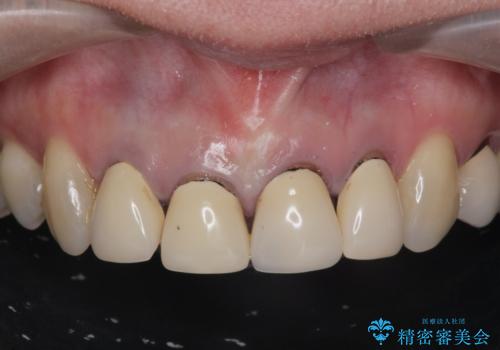

前歯をきれいにしたい

- 「黒ずみの前立つ前歯をやりかえ、きれいにしたい。」と希望され来院されました。

金属色の目立つ前装冠を除去し、発生していた小さな虫歯を丁寧に全て除去しジルコニアセラミッククラウンで審美的な前歯となるような治療を計画します。